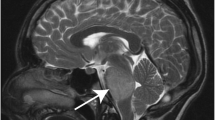

Kinases that regulate cell cycle and mitotic progression are attractive candidates for targeted therapy in a variety of human cancers [31] and have been shown to be potentially important in DIPG [5]. In order to assess the significance these kinases play in the context of DIPG, we analyzed eight patient samples to determine the relative expression of a panel of mitotic checkpoint kinases versus normal brain controls. We found mitotic kinases are upregulated in the tumors versus the controls (p < 0.01), suggesting that they play an important role in DIPG tumorigenesis (Fig. 1a). PLK1, a target with available small molecule inhibitors, was one of the 20 most significantly overexpressed kinases in DIPG compared to normal pons (Fig. 1a). PLK1 transcript was significantly elevated in both patient samples and DIPG cell lines compared to normal brainstem tissue (p < 0.01, Fig. 1b). Gene enrichment analysis of primary tumor microarray data demonstrated PLK1 associated gene signatures including the G2M checkpoint (NES = 1.55, p < 0.05) and mitotic spindle assembly (NES = 1.7, p < 0.05) were also higher in DIPG tumors compared to normal pons (Fig. 1c). Elevated PLK1 protein levels (compared to normal brain) were also identified in two DIPG cell lines DIPG IV and DIPG VI indicating these cells are a good in vitro experimental model to evaluate PLK1 inhibition response (Fig. 1d). Moreover PLK1 protein is significantly elevated in patient samples as shown in Fig. 1e further corroborating the mRNA data suggesting that PLK1 is a potential therapeutic target in DIPG.

PLK1 is overexpressed in DIPG patient samples and cell lines. a Gene expression of a panel of mitotic checkpoint kinases in patients with DIPG versus normal pons. Arrow shows up-regulation of PLK1 in DIPG samples. b Microarray data analysis of PLK1 gene expression in brainstem, patient DIPG samples, and DIPG cell lines. Expression level ± SEM is shown (c) Gene enrichment analysis of patient DIPG samples compared to normal pons from microarray data for PLK1 associated gene signatures. d Confirmation of elevated PLK1 protein expression in DIPG cell lines compared to normal pons and cerebellum (CB) by western blot. e Western blot analysis of PLK1 protein in normal pons and three patient samples